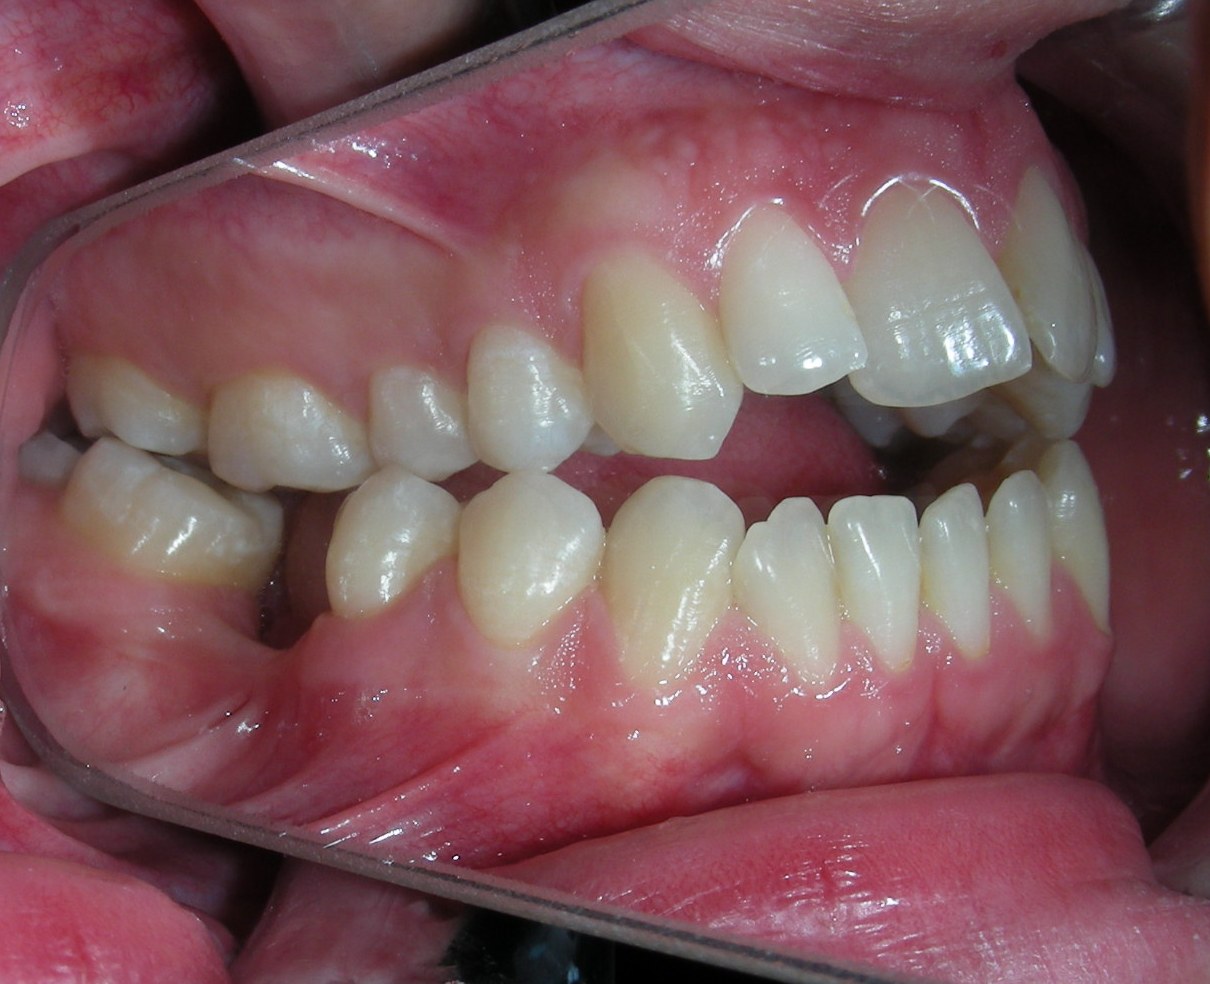

The patient presented with an anterior open bite, characterized by the absence of vertical overlap between the upper and lower incisors, and bilateral posterior crossbite. Extraoral examination revealed a vertically long facial pattern with an increased lower third of the face. The profile is convex with a retruded chin, indicating sagittal and vertical skeletal imbalances. We find also the inclined bipupillary line, which corresponds to facial asymmetries and altered occlusal plane.

Intraoral Examination:

Absent #16, #36 and #46 , No Angle molar relationship . Projection of canines axes in class II relationship . Anterior open bite: Over Bite – 8 mm). Bilateral posterior crossbite: Involvement of upper posterior sectors with inverted buccal-lingual relationship. Moderate Crowding at the level of the upper and lower incisors. Acceptable Oral Hygiene with no periodontal issues